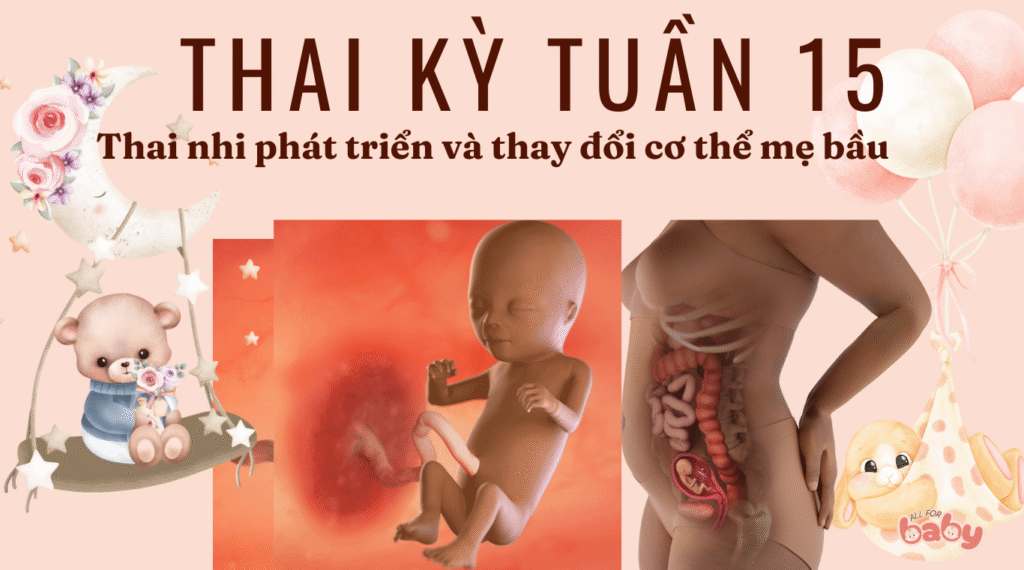

Ở tuần thai thứ 15, bé dài khoảng 10–11 cm (tương đương một quả táo nhỏ) và nặng khoảng 70–80 gam. Những thay đổi nổi bật gồm:

Bé đã có thể cử động các khớp: co duỗi tay chân, xoay người, thậm chí nắm mở bàn tay.

Nụ vị giác bắt đầu hình thành trên lưỡi, chuẩn bị cho khả năng cảm nhận mùi vị sau khi chào đời.

Tai ngoài ngày càng rõ nét và bắt đầu di chuyển về đúng vị trí hai bên đầu.

Xương ngày càng cứng cáp, hệ cơ phát triển mạnh mẽ giúp bé hoạt động linh hoạt hơn.

Bé có thể nghe được những âm thanh mơ hồ từ bên ngoài tử cung.